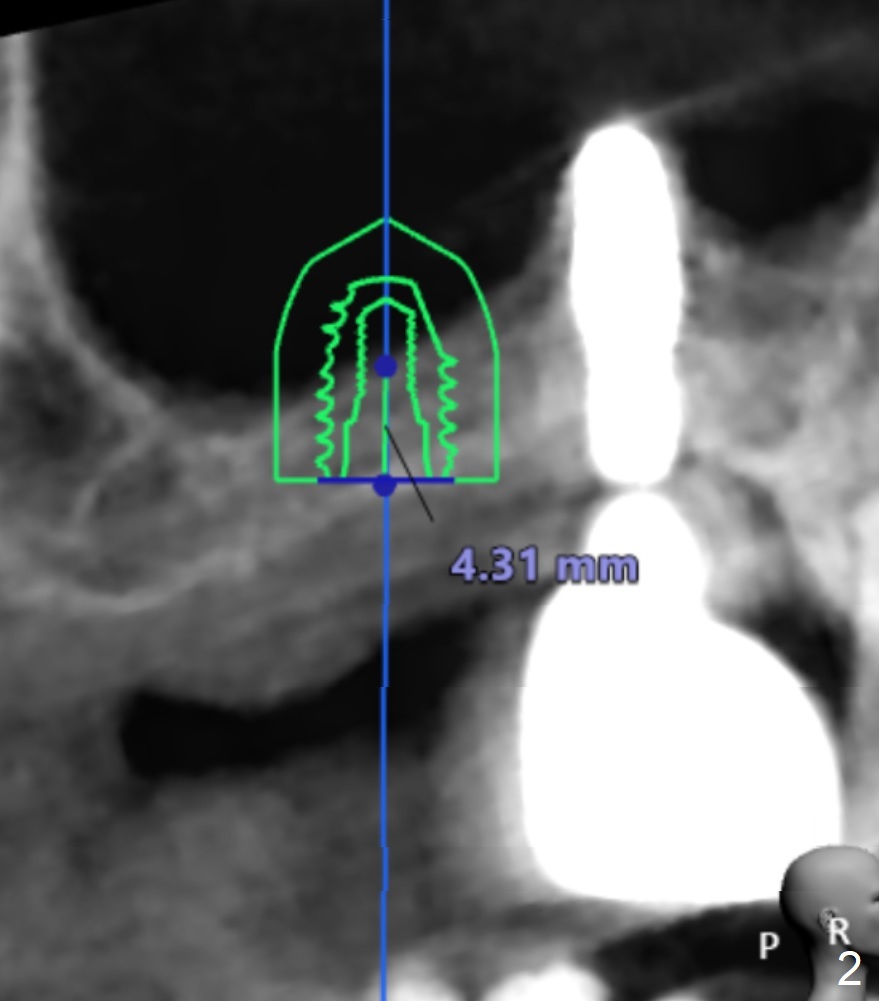

The implant size I tried was 5.0 X 7.3mm and it seems like bone density is quite low.

Undersized drilling suggested (at least 2 size smaller to get more fixation). And on the facial view there's 4mm of remaining bone but on the buccolingual view, there's less than 3mm. It would be much better if you could plan to do a lateral sinus elevation in this case.  Jennifer